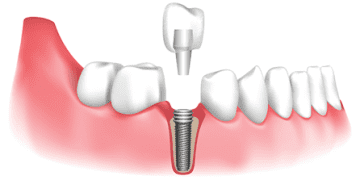

Extraction and Dental Implant: In severe cases, the tooth may be too damaged to be saved and will need to be extracted. The dentist will then place a dental implant in the empty space to help restore proper teeth function.